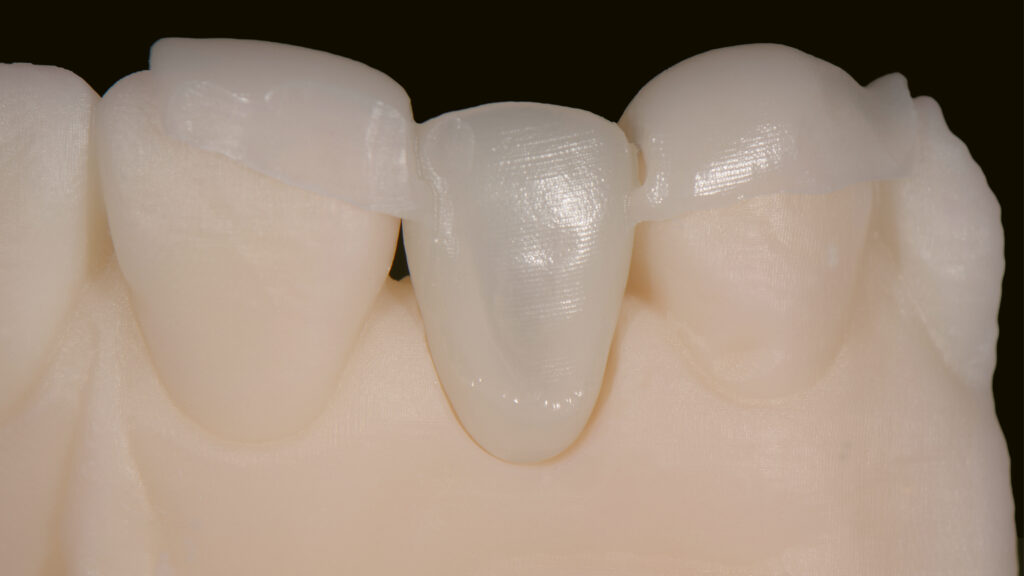

Einer der Vorteile bei der Arbeit mit dem Intraoralscanner ist, dass die digitale Erfassung bei maximaler Okklusion erfolgen kann. Zudem kann die STL-Datei direkt an das Labor übermittelt werden. Die Konstruktion des virtuellen Modells erfolgt mit der Software DTX Studio Design. Anschließend werden die STL-Dateien exportiert und mit einem 3D-Drucker physische Modelle hergestellt (Abb. 5). Um die gescannte Okklusion wiederherstellen zu können, werden die STL-Dateien von Ober- und Unterkiefer getrennt gedruckt. Auf dem Modell wird der Milchzahn regio 12 „extrahiert“ und der periimplantäre Gingivaverlauf ideal gestaltet (Abb. 6 und 7). Höhe und Form des gegenüberliegenden seitlichen Schneidezahns dienen als Vorlage.

Die STL-Datei der provisorischen Implantatkrone wird automatisch erzeugt, ein TempShell (Eierschalenprovisorium) konstruiert und die STL-Datei exportiert. TempShell ist ein verschraubtes Provisorium, das noch am Tag des chirurgischen Eingriffs eingesetzt werden kann. Es wird für jeden Patienten digital erstellt und kann mit DTX Studio Suite einfach an die Implantatposition angepasst werden. Anhand des Datensatzes wird CAD/CAM-gestützt das Provisorium aus PMMA gefräst (Abb. 11). Das gefräste Provisorium (TempShell) hat zwei Flügel. Diese sorgen für die richtige Position und Stabilität im Mund (Abb. 12 und 13). Durch On-Screen-Design-Verfahren passt das Provisorium perfekt auf das gedruckte Modell und in den vorgeschliffenen Gingivaverlauf (Abb. 14).